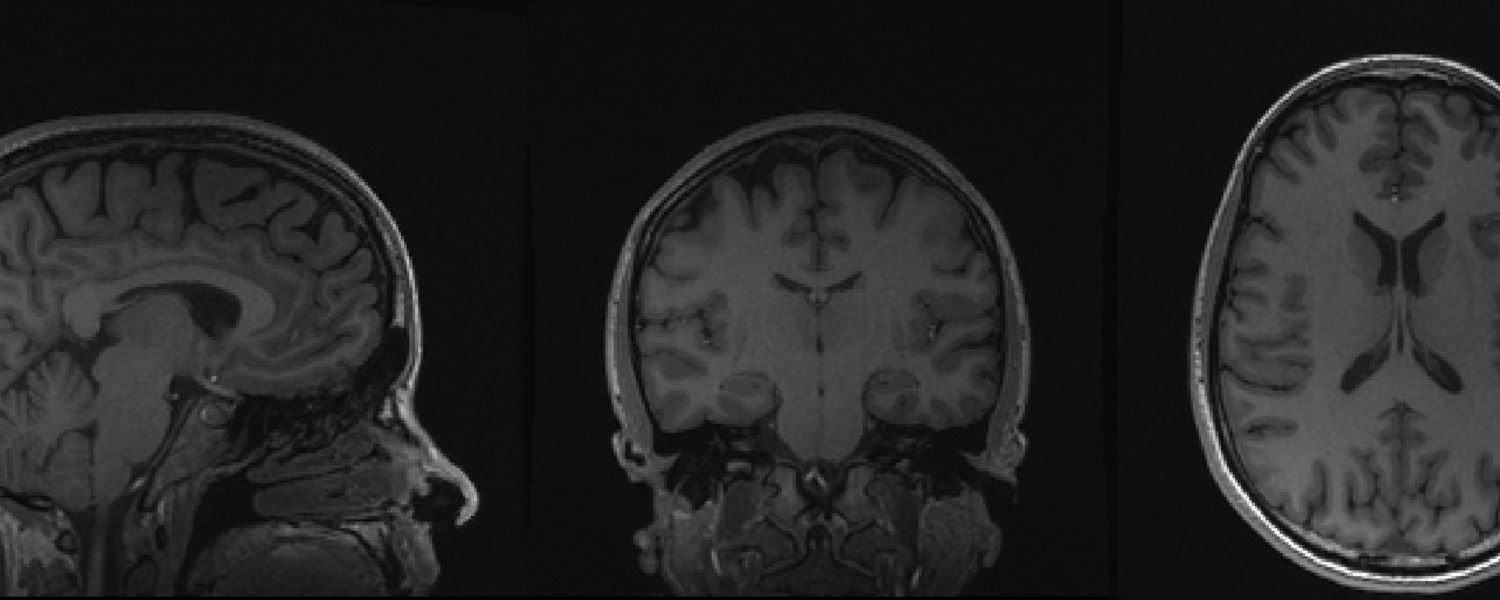

We are an interdisciplinary research group comprised of people with backgrounds in health sciences, engineering, neurosciences and psychology. We study children and adults using multiple modalities, including magnetic resonance imaging and spectroscopy, tactile testing and electroencephalography. Our research is aligned with both the Hotchkiss Brain Institute and the Alberta Children’s Hospital Research Institute and we are located in the Alberta Children’s Hospital.